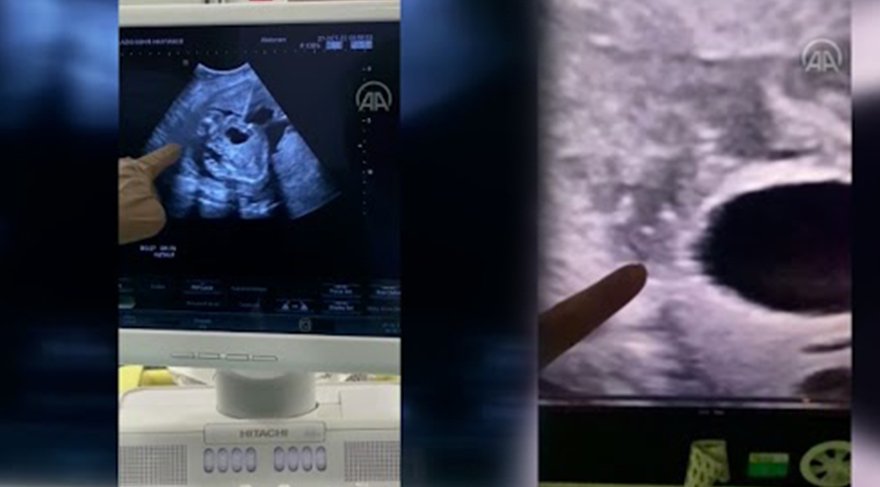

Ultrason eşliğinde vesicoamniyotik stent takılan bebeğin idrarını yapması sağlandı.

"Vesicoamniyotik stent uygulaması ile bebeğin idrar kesesine takılan bir kanül ile idrarını yapması sağlanır. Bu işlemin amacı bebeğin anne karnında içinde bulunduğu suyun devamlılığını sağlamaktır. Bize başvuran gebemizin bebeğinde idrar yolu darlığı tespit ettik. Öncelikle amniyosentez işlemi ile bebeğin genetiğinin normal olduğunu ve yaptığımız tetkiklerde böbreklerinin hala çalışır vaziyette olduğu belirledik. Hastamıza sınırlı bir uyuşturma altında işlemimizi uyguladık. Ultrason eşliğinde yapılan işlem sonucunda bebeğimizin idrarını yapmasını sağladık." AA

Anne karnındaki bebeğe stent takıldı

Elazığ'da anne karnında idrar çıkış yolu darlığı tespit edilen bebeğe stent takıldığı bildirildi.